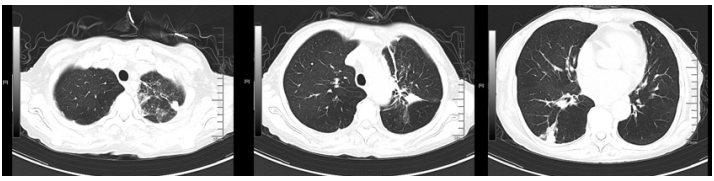

转入我科后患者体温热峰似乎有所下降,但仍有低热。1月27日复查胸部CT可见新冠肺炎病灶吸收、空洞形成,其中见小结节。支持真菌感染(图3)

图片

图3  复查胸部CT(2023-01-27)

7. 病情变化

1月30日开始发热,热峰39℃,伴夜间呛咳。2月1日痰中带血,脓血痰,偶伴小量咯血(10 ml左右)。2月2日胸部CT可见空洞病灶进展(图4)

图4  复查胸部CT(2023-02-02)